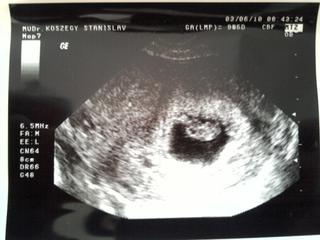

hawajcanka super ze ste v poriadku, fotka je nadherna, neviem sa aj ja dockat buduceho tyzdna.